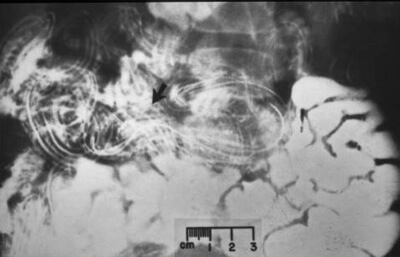

Opravdu je to mytus považovat, že parazity člověka jsou jen hlísti. Existují hodně různorodých parazitů, které žijí v různých orgánech. A které vedou k různým následkům. Ano i hlísti, a přesně škrkavky – jsou nebezpečné. Doslova ničí střeva, vedou k zahnívání a ve výsledku – k smrtlenýmu konci. A ještě, i škrkavky je celkem obtížné najít a odstranit.